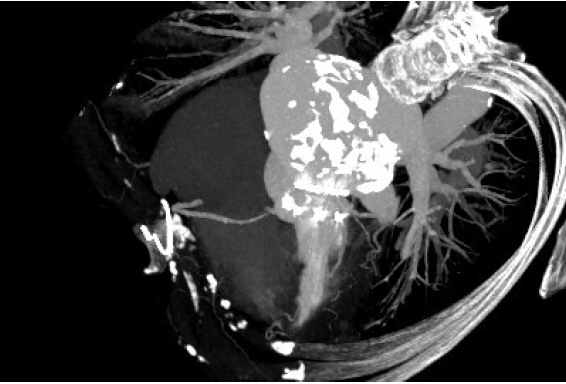

王焱教授教授领衔的结构性心脏病团队对该病例进行了专题探讨,该病例为老年女性,外科生物瓣置换后衰败合并主动脉瓣重度狭窄,既往脑梗死,合并高血压、房颤,肾功能不全等多种基础疾病,一般情况极差。STS评分外科高位,术前CT分析提示左心房大量钙化形成“瓷化心房”,无法耐受传统外科开胸手术。Spaien3 23mm瓣膜模拟植入评估LVOT阻塞风险:1.二尖瓣瓣环与主动脉瓣环平面夹角120.9°>110°;2.瓣膜与室间隔距离最短处6.3mm>6mm;3.测量所有时相中,最小Neo-LVOT面积为188.1mm²>150mm²。经过团队严谨的评估及充分的讨论,决定先行Venus A-Plus 23mm 主动脉瓣置换,再予Spaien3 23mm行二尖瓣置换。